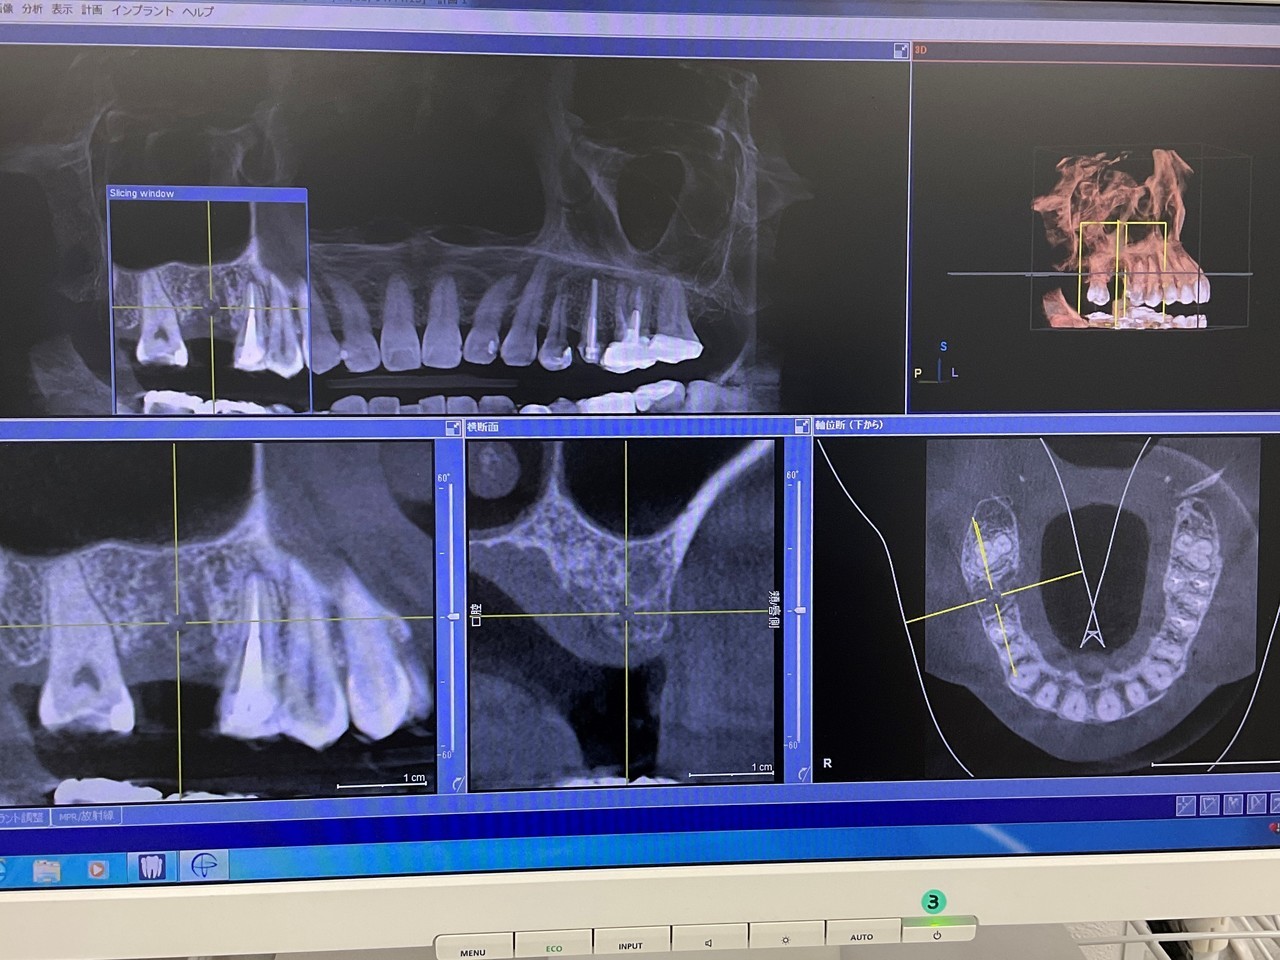

CT撮影

埋入位置を決めるための装置(ラジオグラフィックガイド)を口腔内に入れCTを撮影します。

CT撮影で立体的な顎の骨を確認できます。

CTシミュレーション

CTデータをインプラント解析ソフトに入れ、手術のシミュレーションをします。

・骨の状態を確認し、骨造成が必要か見極めます。

・シミュレーションでインプラントが可能か確認し、インプラントのサイズを調べます。